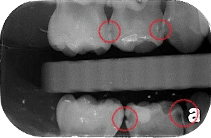

咬翼 X 光片(Bitewing X-rays)

讓醫師評估上顎及下顎的牙冠部分,特別是可以找出牙齒與牙齒接縫處的蛀牙。